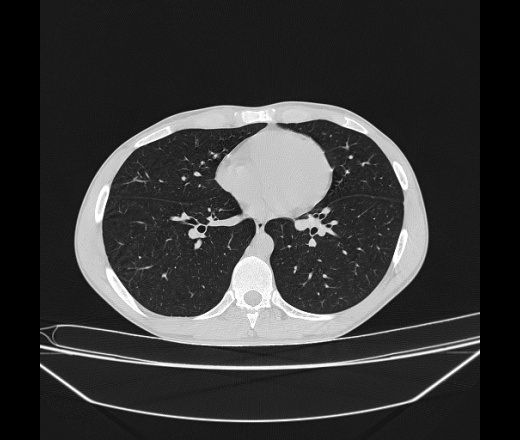

Молодой парень 18 лет, призывник, при прохождении ФЛС на верхушек левого легкого выявили очаги средней интснисвности с нечеткими контурами, тяжи. Сделали бок и томограммы 6-7-8. Везде описывают как очаговый твс. Вижу только перибронхиальный фиброз. Что за изменения в бронхах, указано нижи стрелками, тоже перибронхиальный?

Не стал бы говорить об очагах. Акцентировал бы не на фиброзе, а на тракционных бронхоэктазах. Не обязательно они результат tbc бронхов, но проверить не помешает.

Иван, пациент ведь уже "направлен с ОПТД", так?surprise Возвращайте его назад с заключением о возможном микобактериозе. Остаточные поствоспалительные ( посттуберкулёзные?) в дифряд.Очаговый твс с неясной активностью они уже себе "нарисовали", как я поняла.